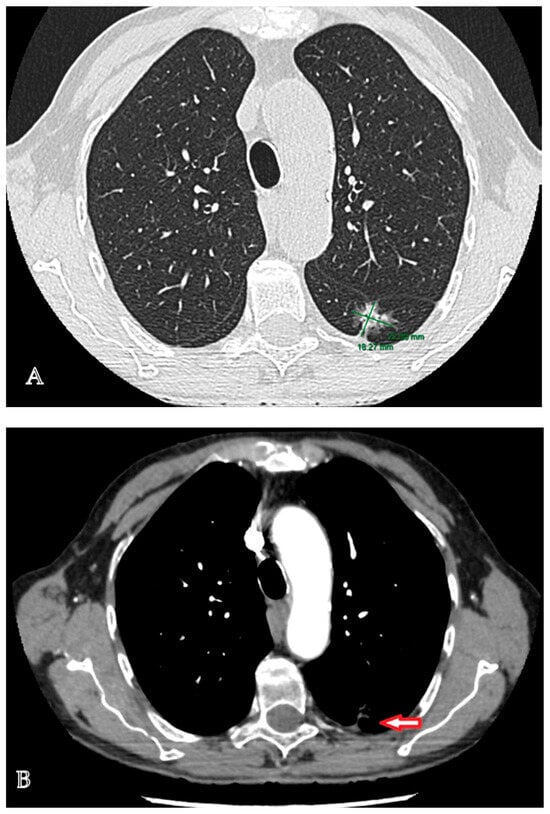

The diagnostic management was continued with a contrast-enhanced computed tomographic (CT) examination of the chest that highlighted a multiseptate lung tumor with multicystic appearance and peripheral gadolinophilia, with maximum dimensions of 41/24/30 mm, located in the lower left lobe, with direct communication to the bronchial lumen, associated with bronchial dilatations and discrete ground-glass areas (Figure 1A–C). In addition, at the level of the left Fowler segment, a partially solid spiculiform image with maximum dimensions of 22/18/20 mm was discovered, with extensions to the parietal pleura and oblique fissure, exerting a retractive effect on both structures (Figure 2A,B). Notably, mediastinal adenopathies were not identified. The suspicion of pulmonary cancer was raised with regard to the second lesion that was previously described.

Figure 2. Lung adenocarcinoma located at the level of the left Fowler segment. (A). Contrast-enhanced chest computed tomography: a partially solid spiculiform tumor with maximum dimensions of 22/18/20 mm, located in the left Fowler segment. (B). Contrast-enhanced chest computed tomography, arterial phase: a partially solid spiculiform tumor that sends extensions to the parietal pleura and oblique fissure, exerting a retractive effect on both structures.